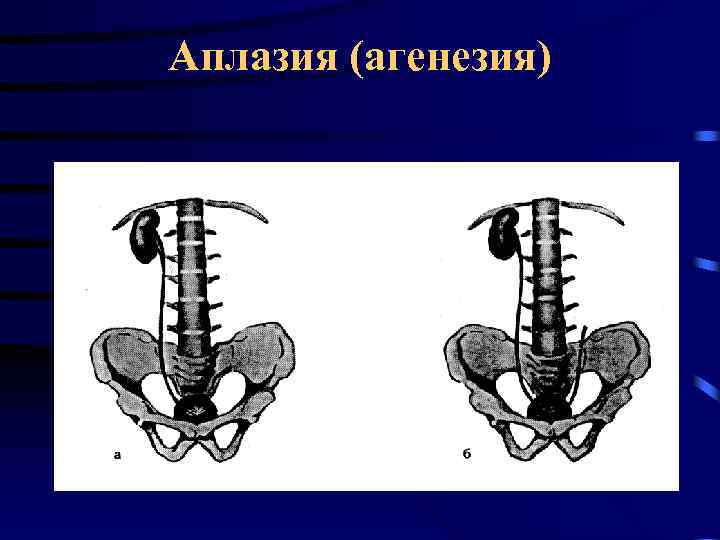

Аплазия (агенезия) • Частота 1: 1000 - 1: 2000 • Диагностика • • • Хромоцистоскопия УЗИ Экскреторная урография КТ Ангиография

Аплазия (агенезия) • Частота 1: 1000 - 1: 2000 • Диагностика • • • Хромоцистоскопия УЗИ Экскреторная урография КТ Ангиография

Аплазия (агенезия)

Аплазия (агенезия)

Аплазия (агенезия)

Аплазия (агенезия)